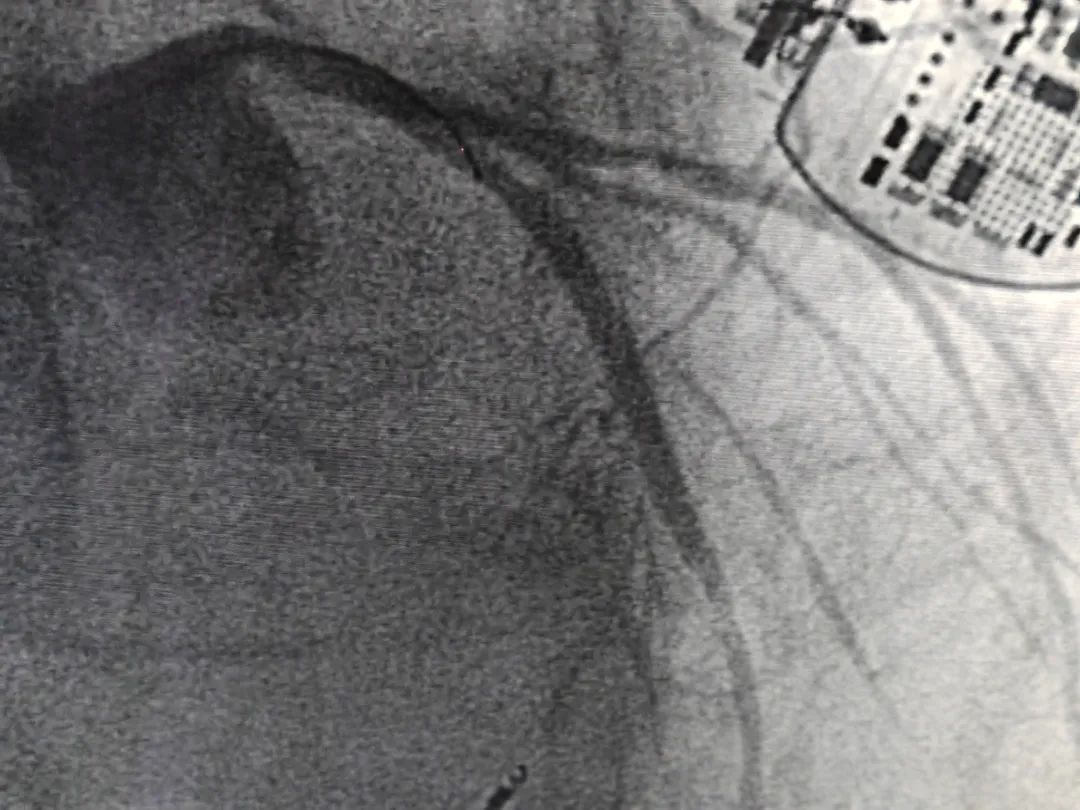

激光成形术后